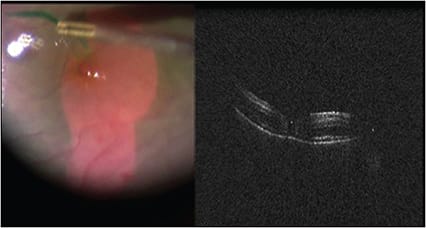

Anterior segment iOCT may also be useful for the retinal surgeon. Here, iOCT of the pars plana immediately after trocar cannulas are removed clearly illustrates the rationale for beveled vitrectomy trocar cannula placement. In this image of the pars plana after the cannulas are removed, an open 25-gauge sclerotomy is present with a small conjunctival bleb (Figure 7). This is in sharp contradistinction to this much more beveled sclerotomy which is closed and does not have an overlying conjunctival bleb (Figure 8, page 52).

Figure 8. With a more beveled sclerotomy, which is closed, there is no overlying conjunctival bleb.